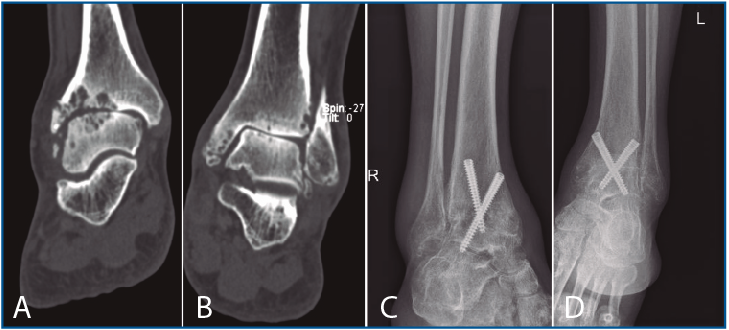

La segunda artrodesis se llevó a cabo durante el año siguiente a la primera intervención. La artrodesis fue tibioastragalina bilateral en 2 pacientes y tibiotalocalcánea (TTC) bilateral en el paciente restante. La estabilización ósea se realizó en un caso con 2 tornillos canulados Acutrak Plus® (Acumed, Hillsboro, EE. UU.) cruzados en ambos tobillos (Figura 1), en otro caso con clavo endomedular retrógrado T2 12 × 200 mm (Stryker, Schönkirchen, Alemania) en ambos tobillos (Figura 2) y en el último caso se utilizaron tornillos canulados Acutrak Plus® cruzados en el tobillo izquierdo y la técnica Putti en el tobillo derecho (Figura 3). La fijación de la artrodesis se realizó con el pie en plantígrado.

Figura 1. Caso 1. Varón de 47 años con artrosis primaria de tobillo bilateral. Corte coronal de tomografía axial computarizada (TAC) del tobillo derecho (A) e izquierdo (B) preoperatorio. Radiografía anteroposterior de artrodesis tibioastragalina con 2 tornillos canulados cruzados en tobillo derecho (C) e izquierdo (D) al año de la última intervención (tobillo derecho).